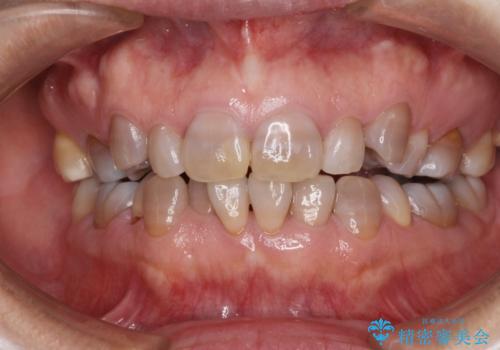

- 小さいころからの歯の変色と矯正治療の後戻りを気にして来院された患者様です。

気になる変色歯を仮歯に変え、その後歯列不正を矯正治療で改善し、最後にオールセラミッククラウンにて補綴治療することとしました。